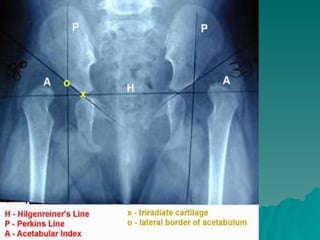

Developmental dysplasia of the hip is a condition where the hip joint is unstable or partially dislocated. It affects 1-50 out of every 1000 live births, with 60% being detected by 1 week of age and 90% by 8 weeks. The document discusses the anatomy, aetiology, pathology, clinical features, imaging, and different treatment approaches depending on if the patient is under 6 months, 6 months to 6 years, or above 6 years of age.